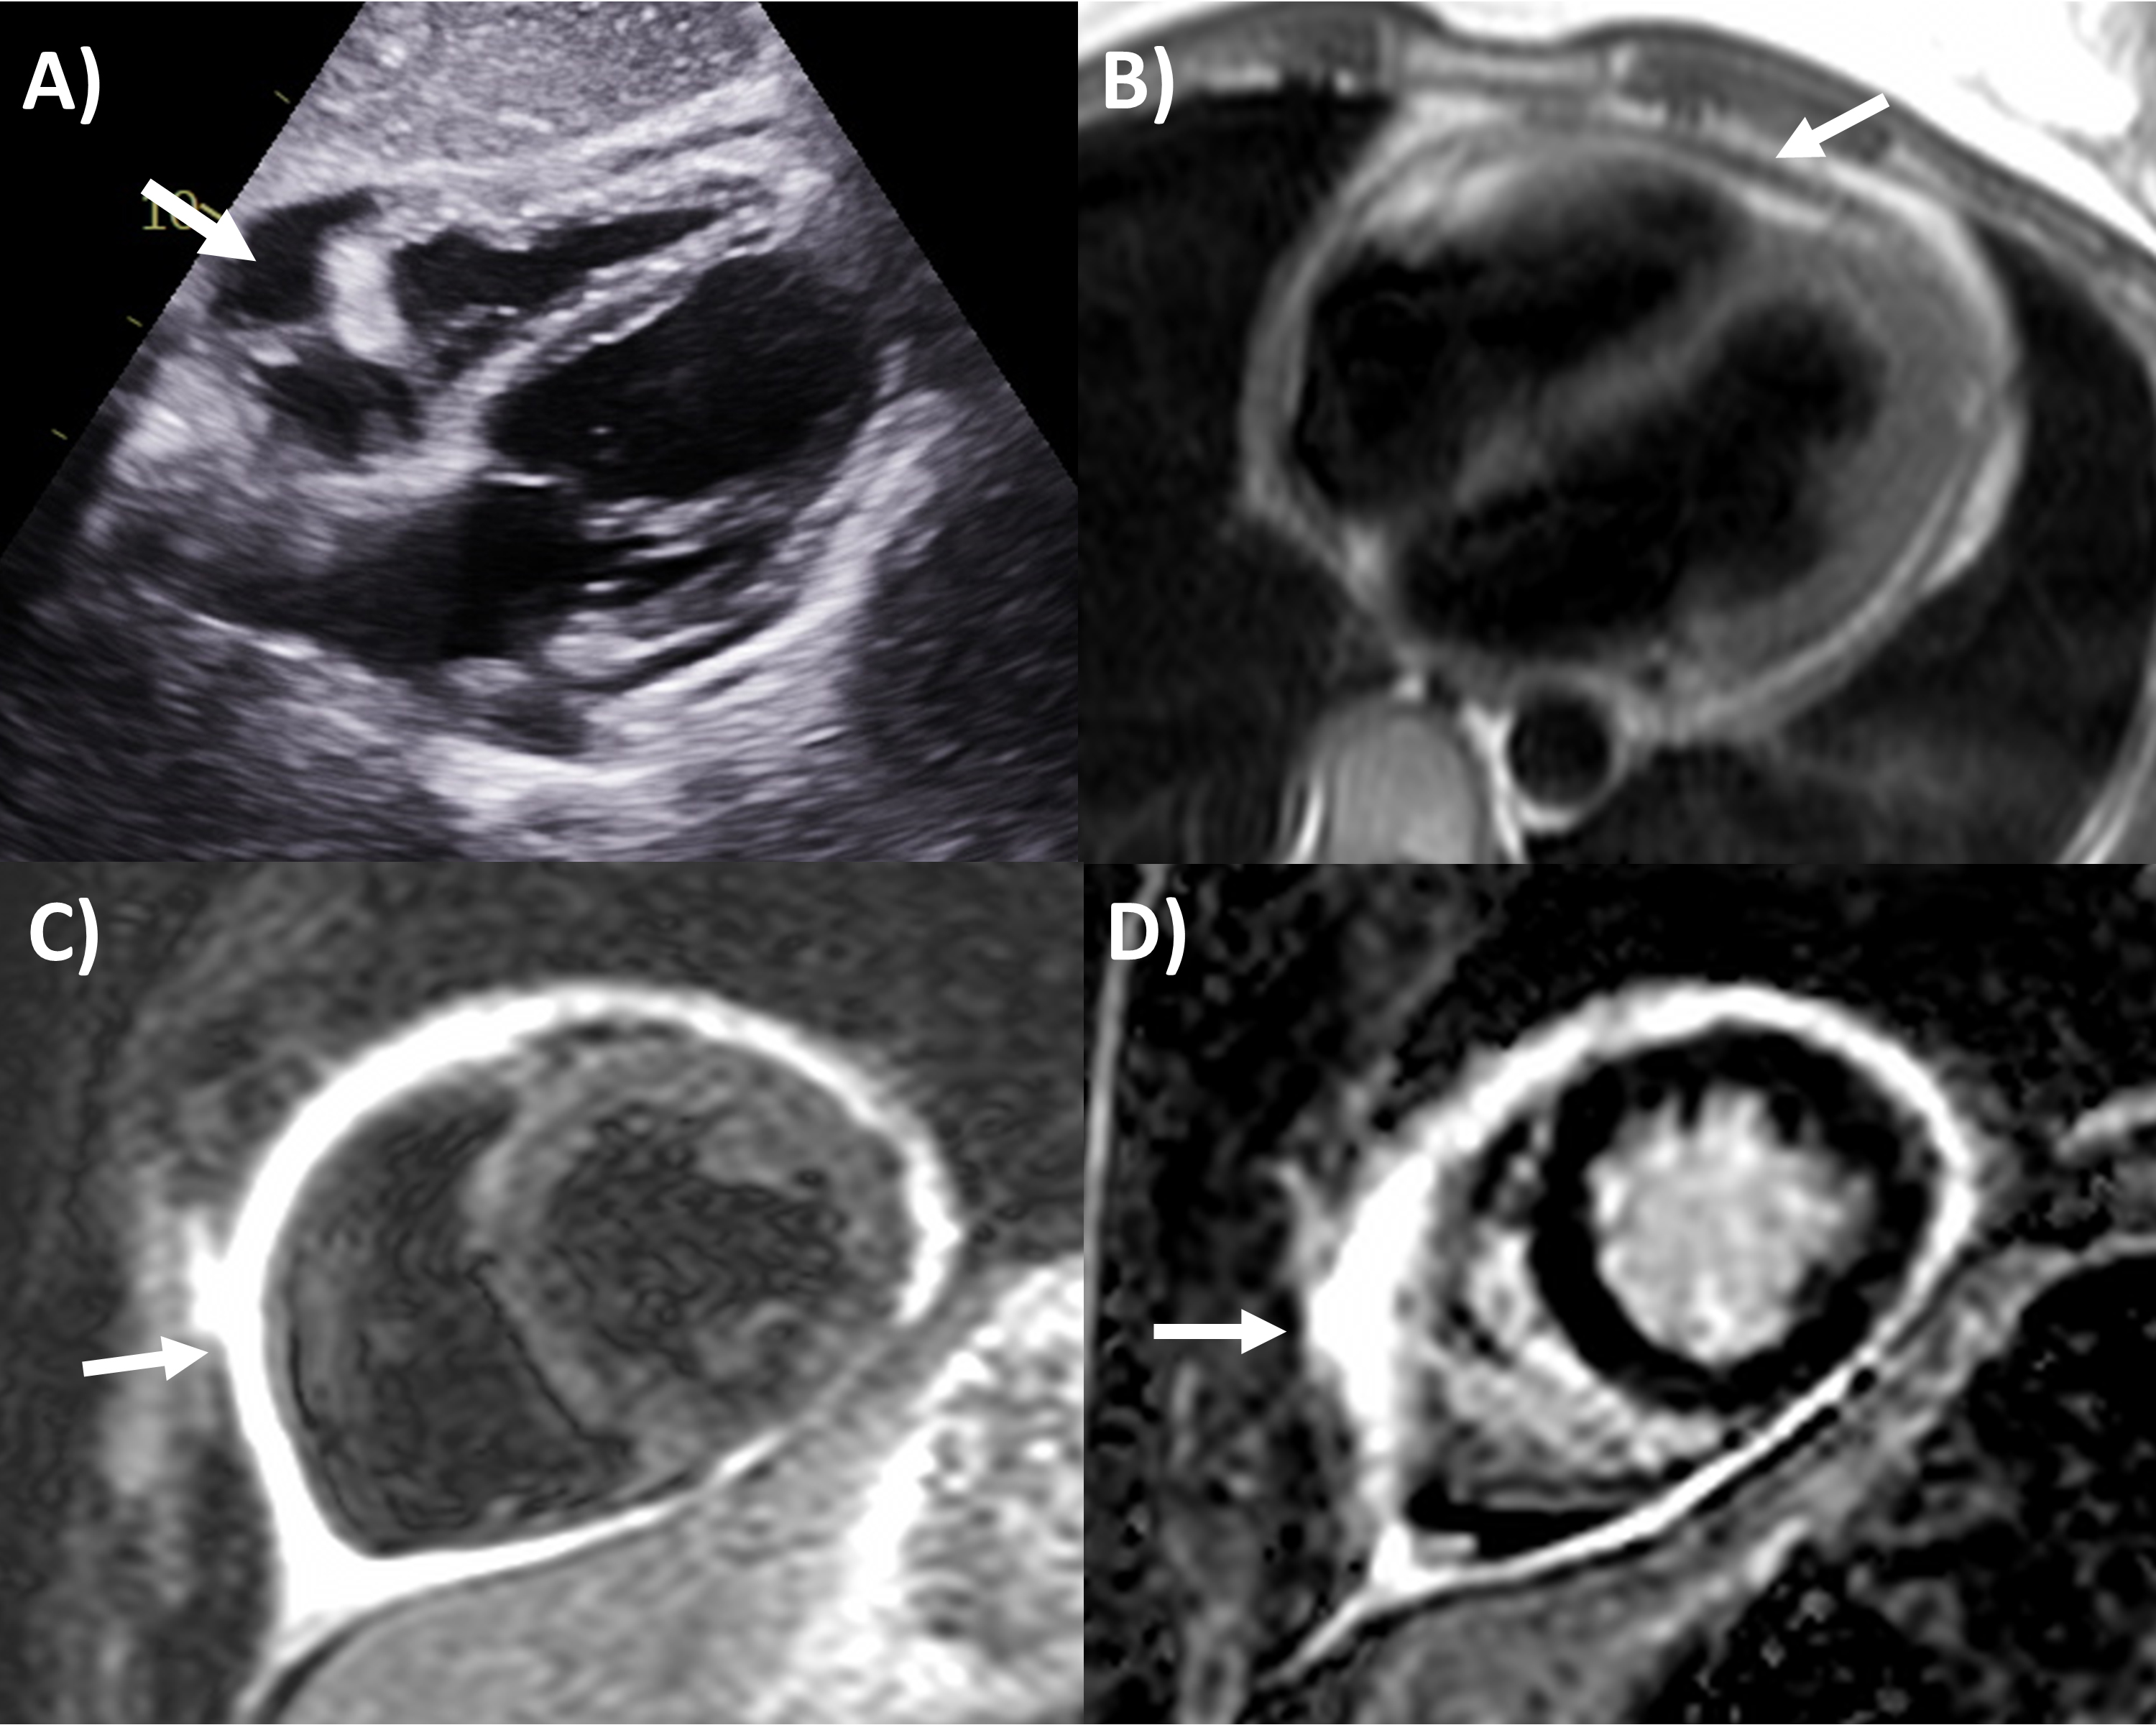

Fig. 1.Multi-modality imaging features of acute pericarditis case. (A) Small pericardial effusion (arrow) subcostal view of echocardiography. (B) Pericardial thickening (arrow) on black-blood spin echo sequence of magnetic resonance imaging (MRI). (C) Severe circumferential increased pericardial signal indicating edema (arrow) on T2-weighted short tau inversion recovery imaging of MRI. (D) Severe circumferential pericardial enhancement indicating inflammation/fibrosis (arrow) on delayed gadolinium enhancement sequence of MRI.

Based on this criteria, echocardiography is the first-line imaging modality recommended for all patients undergoing pericarditis evaluation, although it is often normal [1, 2]. Apart from its main role in identifying pericardial effusion, echocardiography can examine the presence of tamponade physiology present in approximately 3% of acute pericarditis, identify pericardial thickening, evaluate for the presence of regional wall motion abnormalities that may indicate concurrent myocardial involvement (myo-pericarditis) in approximately 5%, or look for alternative diagnoses like acute coronary syndrome or aortic dissection [2]. Echocardiography is also important during follow-up after initial pericarditis event for resolution of pericardial effusion if it had been present, along with signs of constrictive physiology, discussed in the later section.

Perhaps the most important application of MRI in pericardial diseases is its ability to identify pericardial inflammation [2, 10]. The key features include pericardial thickening, best assessed on black-blood spin echo sequences; pericardial edema, assessed using T2-short tau inversion recovery (STIR) sequences as high signal intensity; and inflammation or fibrosis on late gadolinium enhancement sequences again as high signal intensity (Fig. 1) [2, 13, 14]. Histologically, pericardial late gadolinium enhancement correlates with fibroblastic proliferation, neovascularization and chronic inflammation and granulation tissue [15]. Some studies have reported moderate sensitivity (63–68%) and high specificity (up to 100%) of the T2-STIR sequence for acute pericarditis, however this is significantly lower in practice, as elevated signal can also be seen with pericardial effusion or MRI artefact [16, 17]. The delayed enhancement sequence has been reported to have moderate to high 65–100% sensitivity and high specificity 99–100% for pericarditis, however again in practice this is lower with pericardial fat, pleuritis and artefact potentially interfering with scan interpretation, and fat saturated pulses added to delayed enhancement sequences are recommended to improve the positive predictive value of pericardial enhancement [14, 16, 17, 18]. MRI can also evaluate for concomitant myocardial involvement and inflammation (myocarditis) where they be left ventricular dysfunction and regional wall motion abnormalities on cine sequences; increased myocardial signal intensity on T2-STIR or elevated T2-mapping values implying myocardial edema; increased myocardial signal intensity on delayed gadolinium enhancement sequences or elevated T1-mapping values consistent with myocardial inflammation and fibrosis; and along with early gadolinium enhancement suggesting hyperemia [19]. As such MRI is strongly recommended in the initial diagnosis of pericarditis with a complimentary role to clinical, inflammatory biomarkers and echocardiography assessment, especially if the diagnosis remains uncertain after the other tests [1, 2, 10].